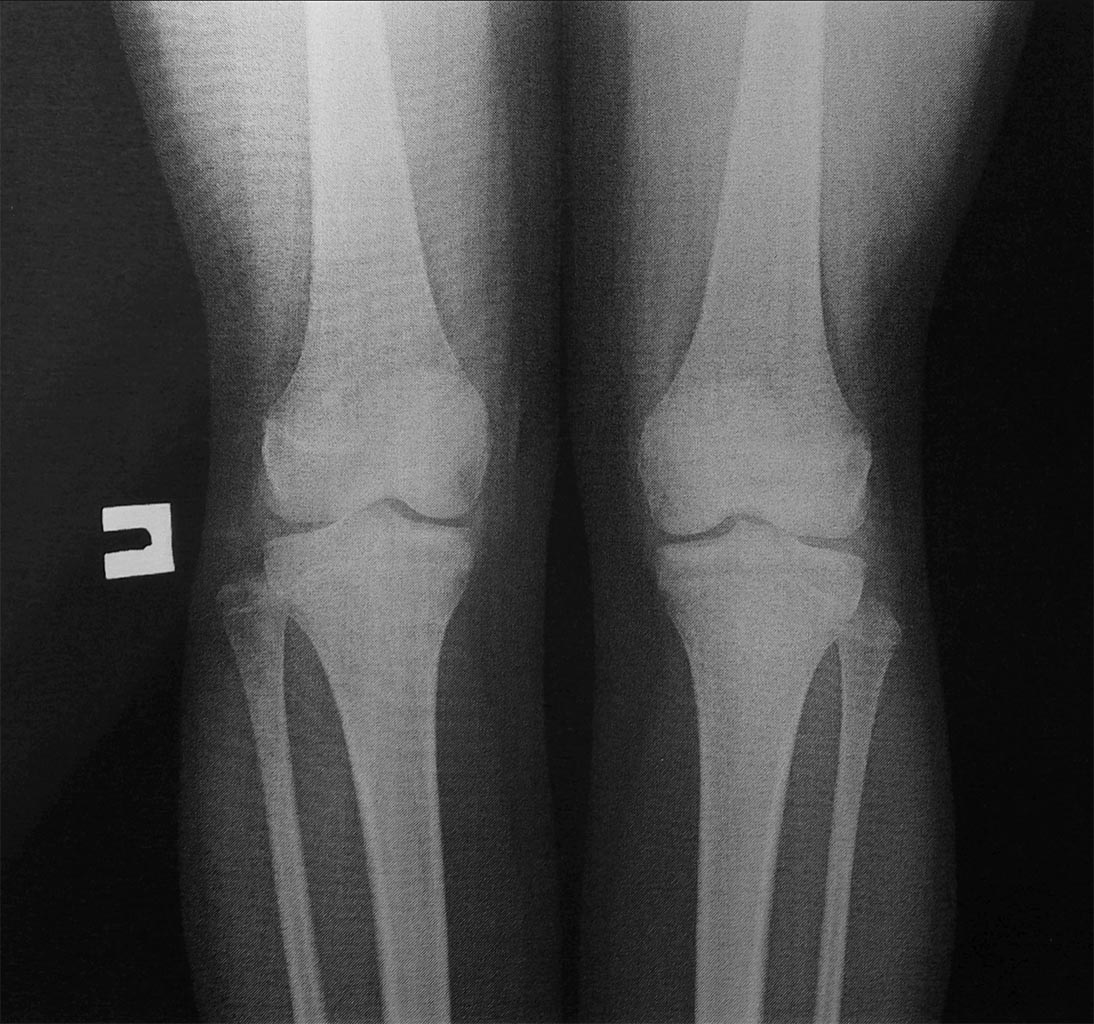

После коррекции суставной площадки большеберцовой кости у нас по прежнему будет сохраняться относительное переудлинение малоберцовой кости с последующим нарастанием клиники невропатии малоберцового нерва. Девочка к нам и обратилась с болями в области колена (в области головки малоберцовой кости) и стопе.

В принципе при удлинении изолированно большеберцовой кости посредством остеотомии в н/3 можно устранить и деформацию суставной площадки.

Оставлять как есть, как то не очень, деформация голеностопного сустава по моему мнению будет только нарастать и дестабилизировать сустав.

Николай. Вы считаете, ещё не поздно выполнить эпифизиодез? Мне казалось на рентгенограммах не прослеживается полоска зоны роста.

Имеющаяся импрессия (или более раннее замыкание росткового хряща) латеральной части эпифиза б/берцовой кости привели к угловой деформации её суставной поверхности на вальгус. Смещению вслед таранной кости мешает лишь более длинная м/берцовая кость. Любое из предлагаемых укорочений м/берцовой или удлинений б/берцовой костей приведёт к вальгусной деформации голеностопного сустава, а желаемый равномерный контакт суставных поверхностей - к манифестации инконгруэнтности и артроза. Исход вполне предсказуемый! Предлагаемая Ниязом клиновидная остеотомия биомеханически вроде более обоснована, однако в конкретном случае действительно сложна , и результат непредсказуем.

Из-за травмы ростковой зоны большеберцовая отстала от нормального развития, и эта диспропорция костей привела к тому, что малоберцовая принимает активное участие в распределении нагрузки. Дистальное сочленение лучше выдерживает нагрузку и поэтому латеральная лодыжка гипертрофируется. Продолжающаяся нагрузка выталкивает из ложа головку малоберцовой вверх, переводит в подвывих и поэтому появляется боль с характерным выступающим контуром головки!

Примерно такой феномен часто наблюдается при лечении методом Илизарова ложных суставов или переломов большеберцовой кости, где сросшаяся или неповрежденная малоберцовая действует как подпорка или выталкивает головку верх. Кстати, степень вывиха головки зависит от позиции сустава, в межберцовом сочленении встречается горизонтальное, косое и вертикальное положение. При горизонтальном трудно создать компрессию в большеберцовой, а косой или вертикальный тип позволяют компрессию, но с вывихом головки, иногда на 1.5-2.0 см. (снимки форм проксимального сочленения приложены)